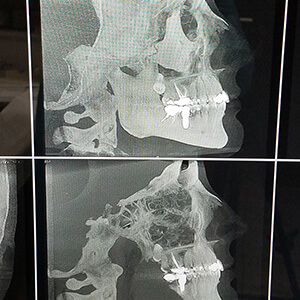

The most accurate form of x-ray imaging currently available is the CT scan, commonly known as a CAT scan or Cone Beam CT scanners (CBCT). Medical CT scanners are often used by Dr. Roshkovan to diagnose, analyze and devise treatment plans for implant surgery.

CBCT scanners use significantly less radiation and may be available to you at Dr. Roshkovan Dental Implants office. Both types of CT scanners provide very detailed, three-dimensional (3-D) images that can accurately measure the height and width of available bone, as well as locate the nearby anatomic structures (such as the maxillary sinuses and mandibular nerves) that the Dr. Igor Roshkovan DDS, MSc must be mindful of during surgery.